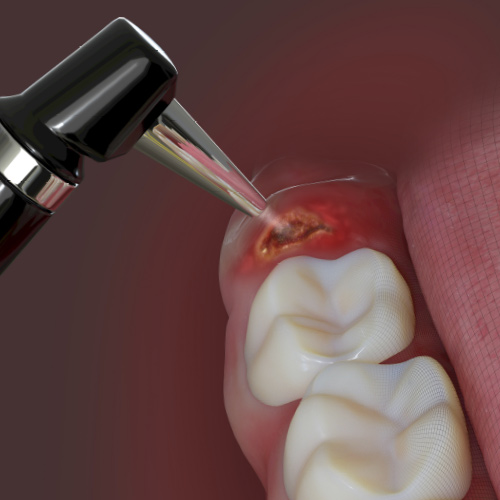

One-Day Endo-Restorative Treatment: The Integration of Advanced Technology and a Single-Visit Workflow for General Dental Practitioners

Scott Sayre, DDS, MBA, MAS

Monday, February 26, 2024

This Compendium eBook offers a continuing education (CE) article that explores the integration of technology as part of a single-visit workflow for root canal therapy that can be implemented by the general dentist. Download to earn 2 complimentary CEU now!